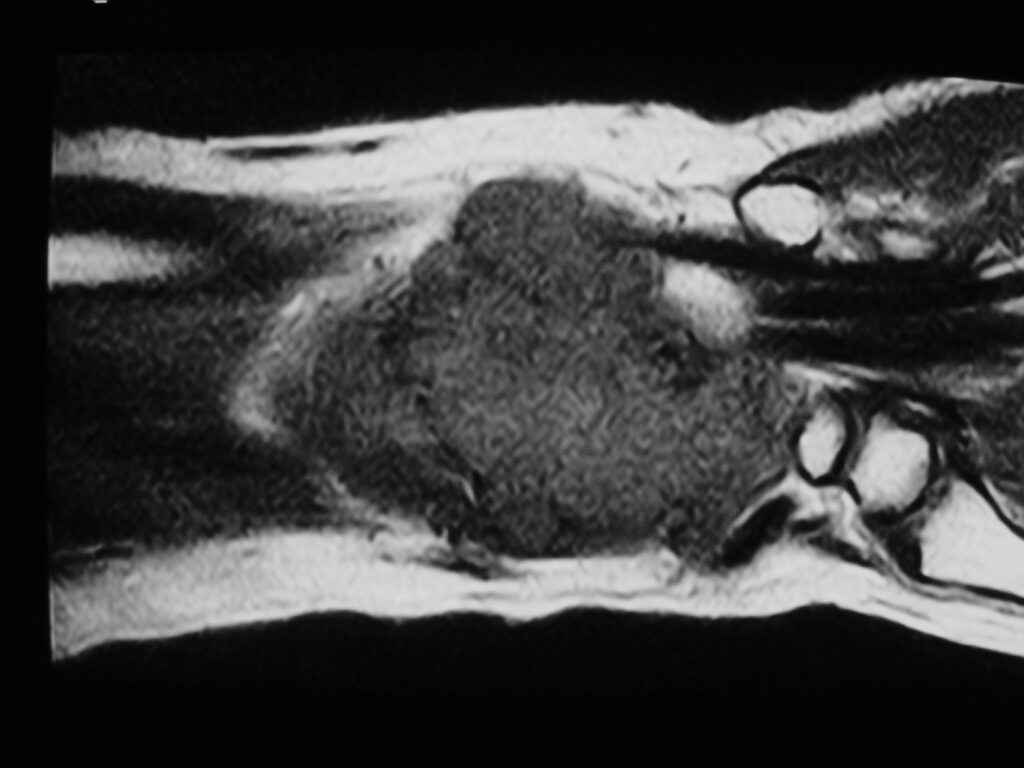

MRI

Shows multiloculated, heterogeneous mass.

“Triple Signal Intensity sign”; hypointense, isointense and hyperintense with fat on T2 – weighted MRI imaging. This sign is present in 30 to 50% of the cases. (Fig.3)

Under contrast enhancement Synovial Sarcoma appears heterogeneous and demonstrate areas of nodular enhancement.

In approximately 30% of cases a multiple vascular cannel may be identified

Synovial sarcomas may have a cystic appearance and are often mistaken for ganglion cysts especially those adjacent to tendons and in the foot and ankle.